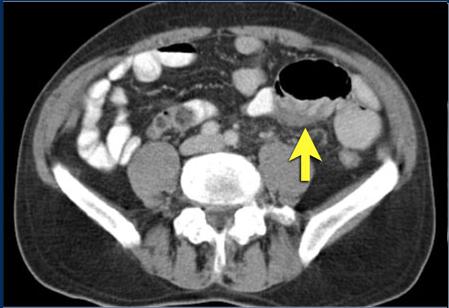

Image d'une masse

fibreuse desmoplastique retractile mesenterique (

fleche jaune ) avec des nodules de calcifies.

Diagnostic de tumeur

carcinoide : Masse tumoral particuliairement de

l'intestin , image de metastase , et syndrome de

secretion serotonine :

Diarrhee , HTA ou hypoTA

de persitante , tachycardie et bronchospasme |